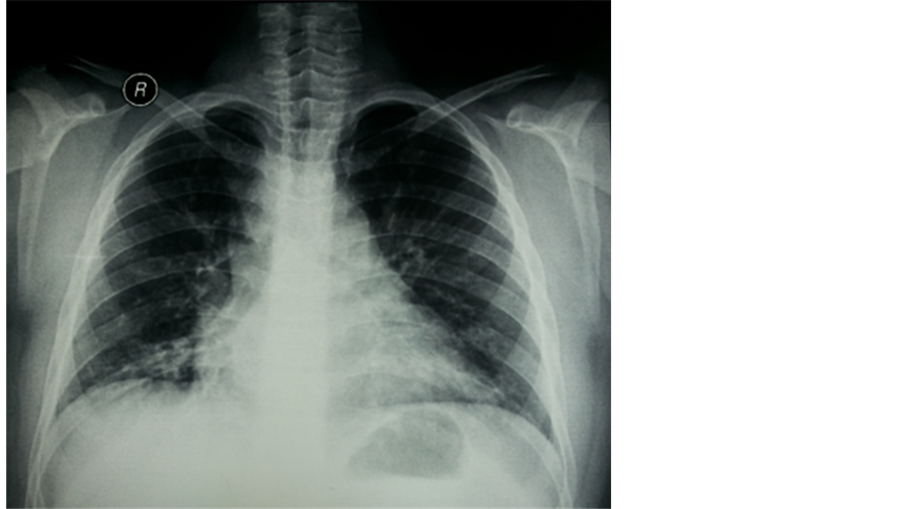

Physical examination showed that the patient was alert, had tachypnea, tachycardia. He looked weak and cyanotic, without noticeable dysmorphic appearance. He was overweight (45 kg and 142 cm high) and microcephaly. On heart auscultation, there was no audible murmur. Laboratory findings were unremarkable. Chest radiograph showed slightly increased pulmonary vascular marking with cardiomegaly (Figure 1), while electrocardiography revealed right axis deviation and right ventricular hypertrophy without strain. Echocardiography demonstrated mild tricuspid regurgitation, severe pulmonary hypertension, good left and right ventricular contractility; no intracardiac defect was found. The patient was initially diagnosed with heart failure due to idiopathic pulmonary arterial hypertension (PAH). To exclude abnormalities in the lungs and heart, the patient underwent chest CT, spirometry, sputum analysis, and right cardiac catheterization. He was treated with sildenafil and furosemide as we explored the etiology of PAH.

Figure 1. Chest radiograph showed increased pulmonary vascular marking, cardiomegaly, no pulmonary edema, and cuffing sign (white arrows).